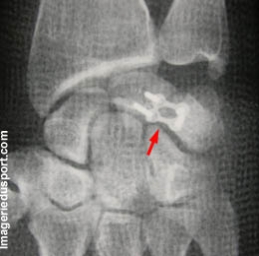

A - Radiographie standard de face : Contrôle post-opératoire immédiat (au bloc) d'une arthrodèse carpienne luno-triquétrale. Controle du rétablissement des arcs de congruence.

B - Radiographie standard de profil : Bonne position du matériel de synthése.

Arthrodèse luno-triquétrale dans le cadre d'une instabilité de cette articulation. Lors de l'intervention, présence associée d'une lésion du ligament scapho-lunaire, mais d'aspect stable.